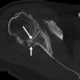

Shoulder defect

Shoulder problems including pain, are one of the more common reasons for physician visits for musculoskeletal symptoms. The shoulder is the most movable joint in the body. [Source: Wikipedia ]